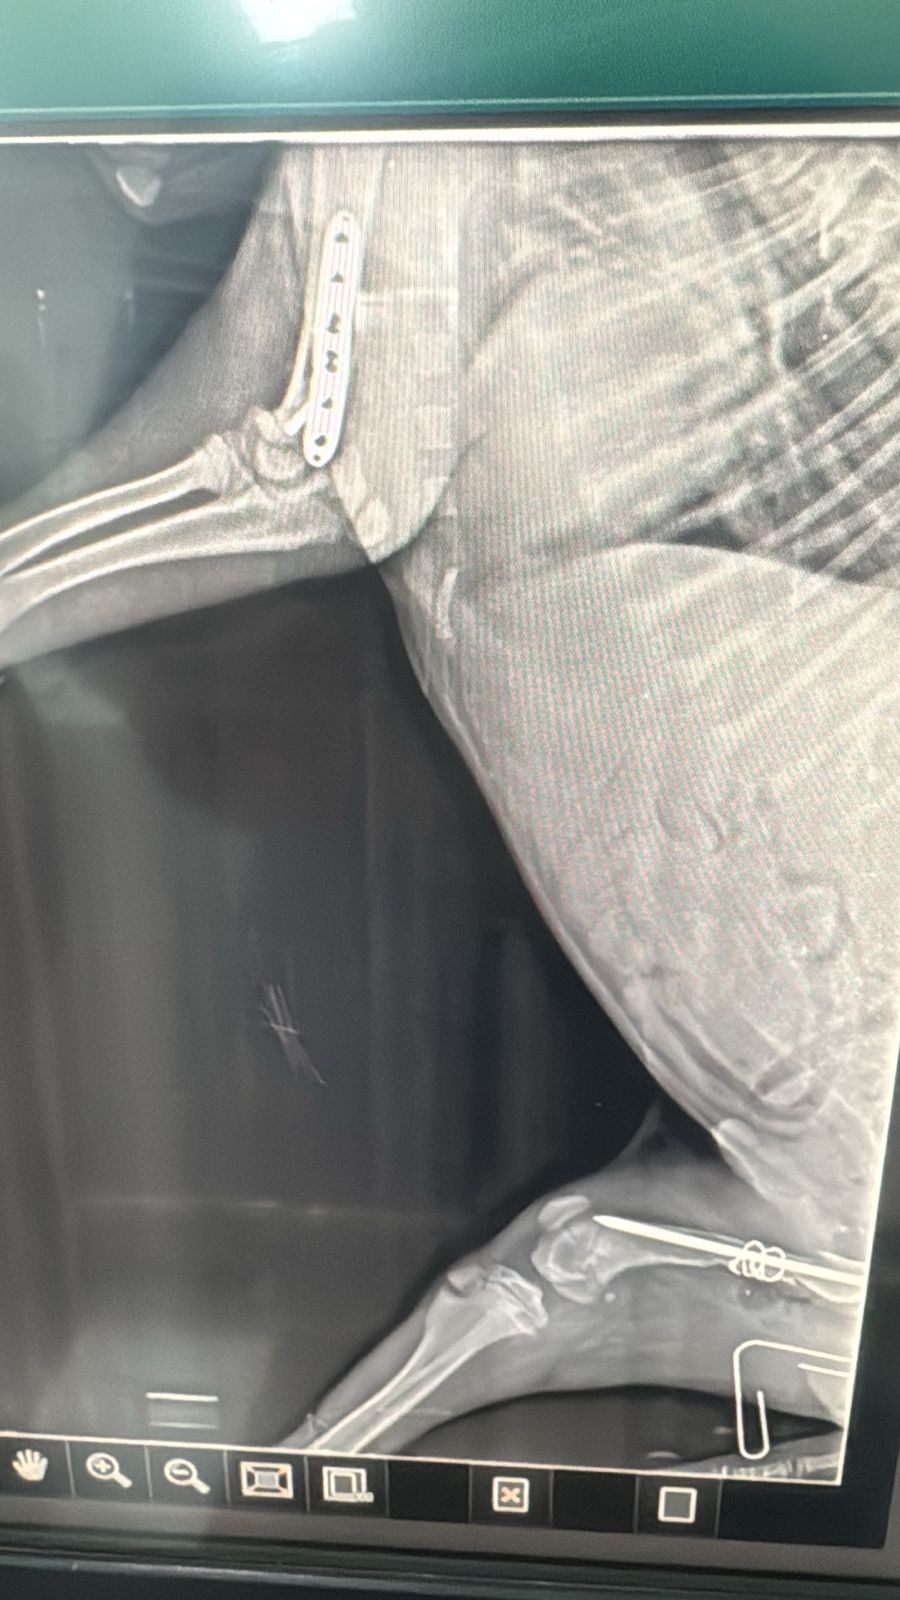

Legend was hit by a car, he had broken front and back legs. His recovery was long after 2 surgeries. He was rescued from the Chouf, laying on the side of the road under the rain. DOB: 24/8/2024